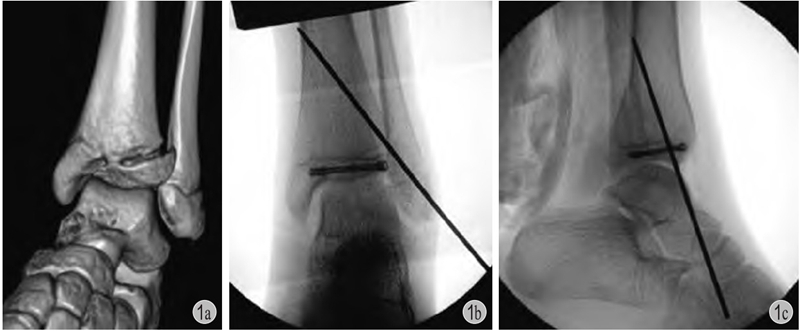

螺钉适应证主要有骨骺和干骺端骨折、关节内骨软骨骨折、牵拉骨骺的撕脱骨折以及脊柱矫形、骨盆截骨处固定等,也可应用于生长导向治疗。一般而言,螺钉禁止穿越骺板固定。加压螺钉临床应用广泛,比如儿童胫骨远端骨骺骨折时,可使用空心螺钉平行骺板加压固定(图1);股骨颈骨折、股骨头骨骺滑脱时,可使用半螺纹或全螺纹变距螺钉加压固定;髋关节发育不良行三联截骨时,也可用全螺纹螺钉固定髂骨截骨端。可吸收钉棒系统主要用于关节内骨软骨骨折、牵拉骨骺撕脱骨折等,虽然可降解不用二次手术取出,但固定牢固性相对于金属螺钉弱,需要术者有所考虑。膝关节等关节面骨折可选用多枚可吸收棒固定,临床效果尚可。金属螺钉置入时要考虑取出时容易寻找,尤其是全螺纹无头空心钉。青少年股骨颈骨折及股骨头骨骺滑脱术后2年以上取螺钉会较为困难,可以早些取或者不取出。

图1 患儿,女,12岁

a:左胫骨远端三平面骨折;b、c:切开复位,空心钉 + 克氏针固定,空心钉平行骺板且位于骨骺内,辅以斜行克氏针穿越骺板固定